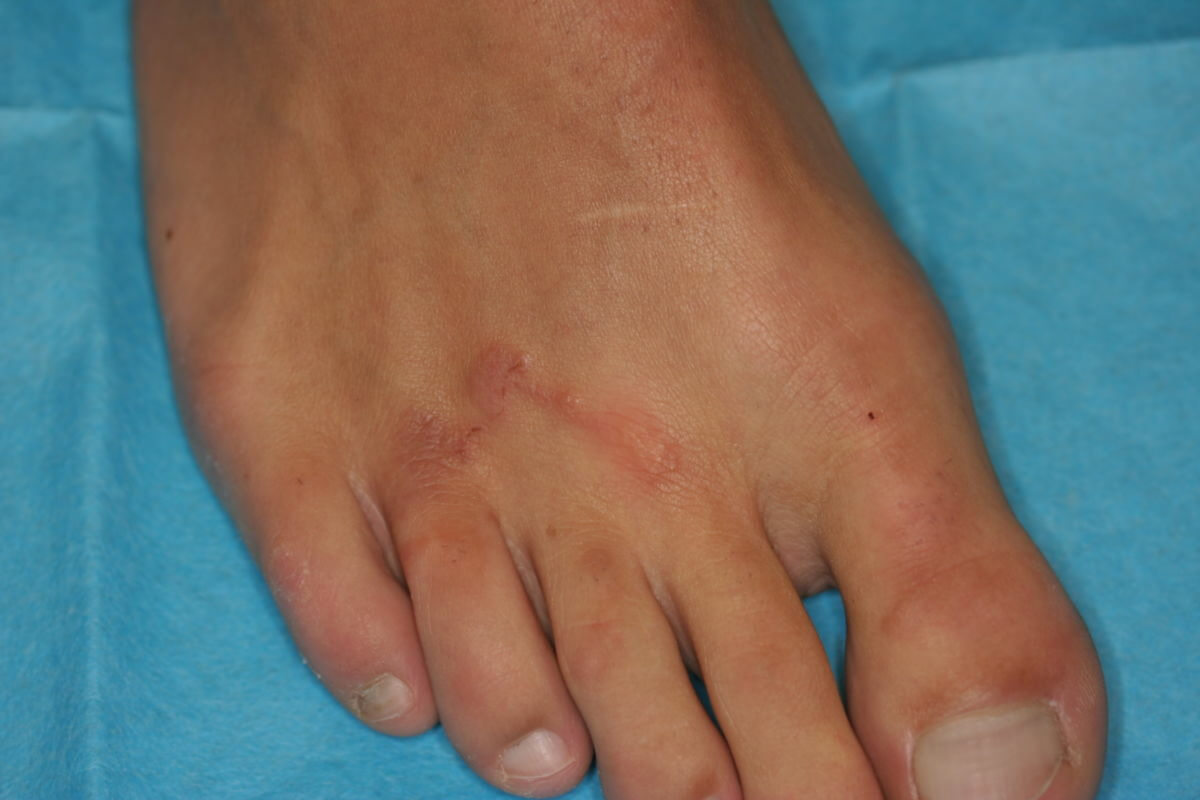

Kaum etwas sorgt am Strand so zuverlässig für Panik wie eine rote geschlängelte Linie unter der Haut, die langsam, aber sicher länger wird. Larva migrans cutanea, meist durch Hakenwurmlarven (Ancylostoma) von Hunden oder Katzen verursacht, ist das Paradebeispiel für unerwünschte Mitbringsel. Die Infektion erfolgt oft ganz banal: barfuß über tropische Strände laufen, auf denen Hunde und Katzen ihre Spuren hinterlassen haben. Die Larven dringen durch die Haut ein und wandern herum. Die Patienten zeigen meist reichlich irritiert ihre „künstlerischen“ Linien, die unter Juckreiz den Unterschenkel dekorieren – ein dermatologischer Notfall ist es selten, aber ein echter Showcase für die tropenmedizinische Sprechstunde. Therapie? Nach einigen Wochen stirbt die Larve sowieso. Und Anthelminthika wie Albendazol oder Ivermectin bringen die Linie schnell zum Stillstand – so auch im Fall unserer Yogalehrerin, die sich völlig zu Recht vorgestellt hat.

Larva Migrans am Fuß – Credit: DocCheck Flexikon